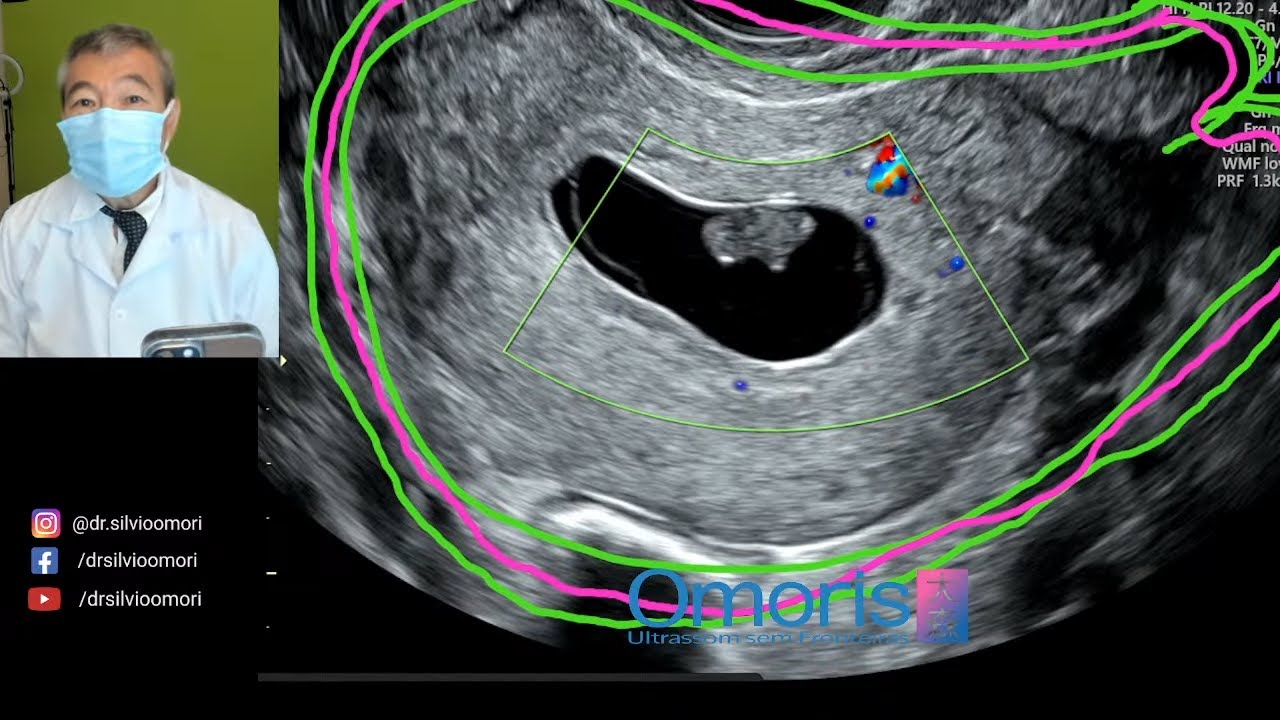

dor muito forte no útero e começa a ter uma uma febre na mãe a operação exame de sangue isso a gente começa a suspeitar de uma infecção ovular e que acaba gerando um aborto se a infecção for bem no início da gestação e depois disso a gente vai ter o aborto retido completo e incompleto mas é mais ou menos a mesma doença a diferença é quando a gente descobriu por exemplo o aborto retido é quando a mulher não sente absolutamente nada e fez um exame e descobriu que o bebê não tá mais com batimentos ou

então que simplesmente não desenvolveu embrião esse seria um aborto retido é muito comum porque agora a gente faz a ultrassom com frequência né antigamente era mais raro porque ultrassom quase ninguém fazia então só descobrir quando a mulher já tava perdendo o bebê mesmo agora não a gente descobre bem cedo e o aborto retido a gente tem duas possibilidades de tratamento uma delas é esperar até e o corpo tentar eliminar e isso é possível de ser feito não é um absurdo em alguns países o protocolo é esperar até oito semanas para ver se o corpo vai

a gente faz a ultrassom e já não enxerga mais sinais de gestação ele dentro e o aborto incompleto é Quando o colo do útero fechou mas ainda ficou coisa lá dentro ainda a gente consegue no ultrassom encontrar uma material com mais de 16 mm mais de 1 cm seis dentro do útero e quando a gente vê um aborto incompleto a gente é sim obrigada a fazer procedimentos eu vou conversar com você sobre o aborto no a curetagem e aspiração não existe a ameaça de aborto né a ameaça de aborto é quando a mulher tem na